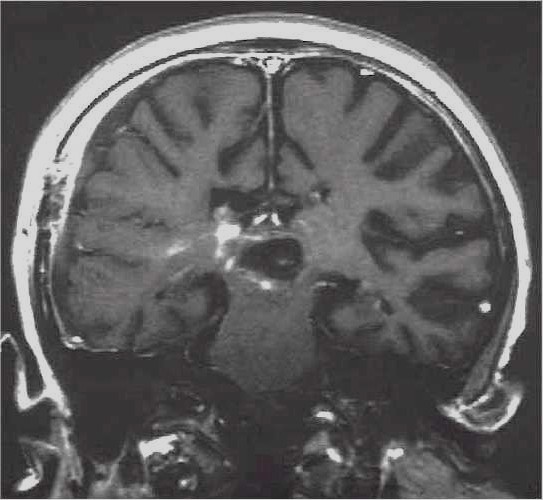

Lesioni caratterizzate da un accrescimento veloce con infiltrazione del tessuto cerebrale attiguo e diffusione a distanza di cellule maligne.

Scopo della chirurgia è ridurre macroscopicamente la massa tumorale per facilitare ulteriori trattamenti (principalmente radio - chemioterapia mentre altri protocolli terapeutici sono ancora in fase di studio).

In queste lesioni la loro conformazione anatomica, praticamente sempre di tipo II (Daumas-Duport) non ha un ruolo così dirimente nell'indicazione chirurgica poiché il comportamento biologico è sicuramente il fattore più importante.

RM:

glioma con segni di trasformazione maligna